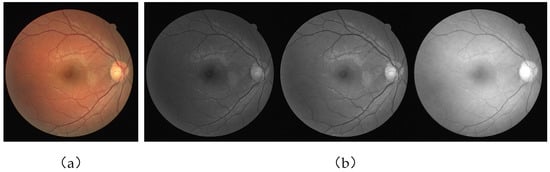

Figure 5 is a partial sample image of both datasets.

Figure 5. (a) DRIVE dataset and (b) CHASE_DB1 dataset. Looking from left to right, the leftmost column is the original image, the middle column is the corresponding ground truth, and the rightmost column is the corresponding mask.